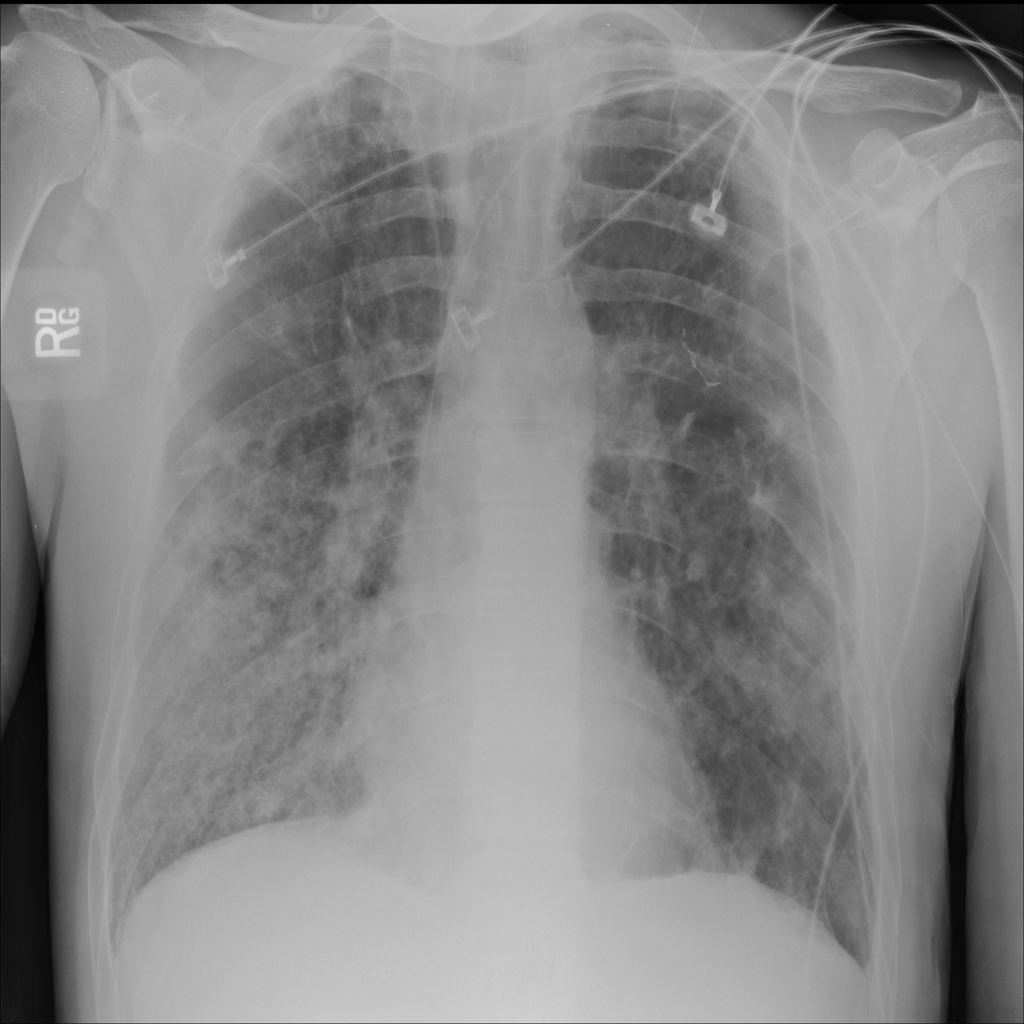

Showing up to 90 reference images for Nodule.

PAT-FB8F · IMG-000Nodule

PAT-FB8F · IMG-000

PA